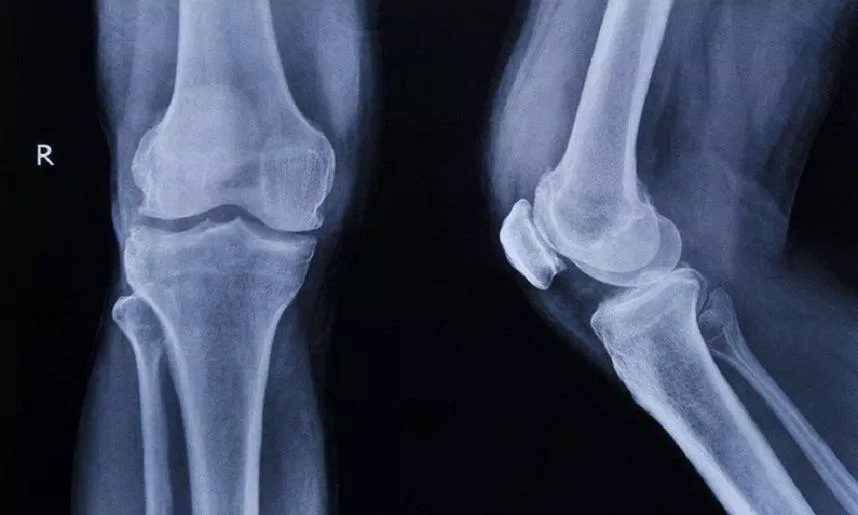

Chẩn đoán hình ảnh phát hiện viêm khớp

Chẩn đoán hình ảnh có thể giúp bác sĩ có cái nhìn rõ ràng về xương, khớp và mô mềm của bạn. Chụp X-quang, MRI hoặc siêu âm có thể cho thấy tình trạng:

- Gãy xương hoặc trật khớp có thể gây đau khớp

- Tổn thương sụn xung quanh khớp

- Chấn thương cơ, dây chằng hoặc gân ở gần khớp

- Viêm mô mềm